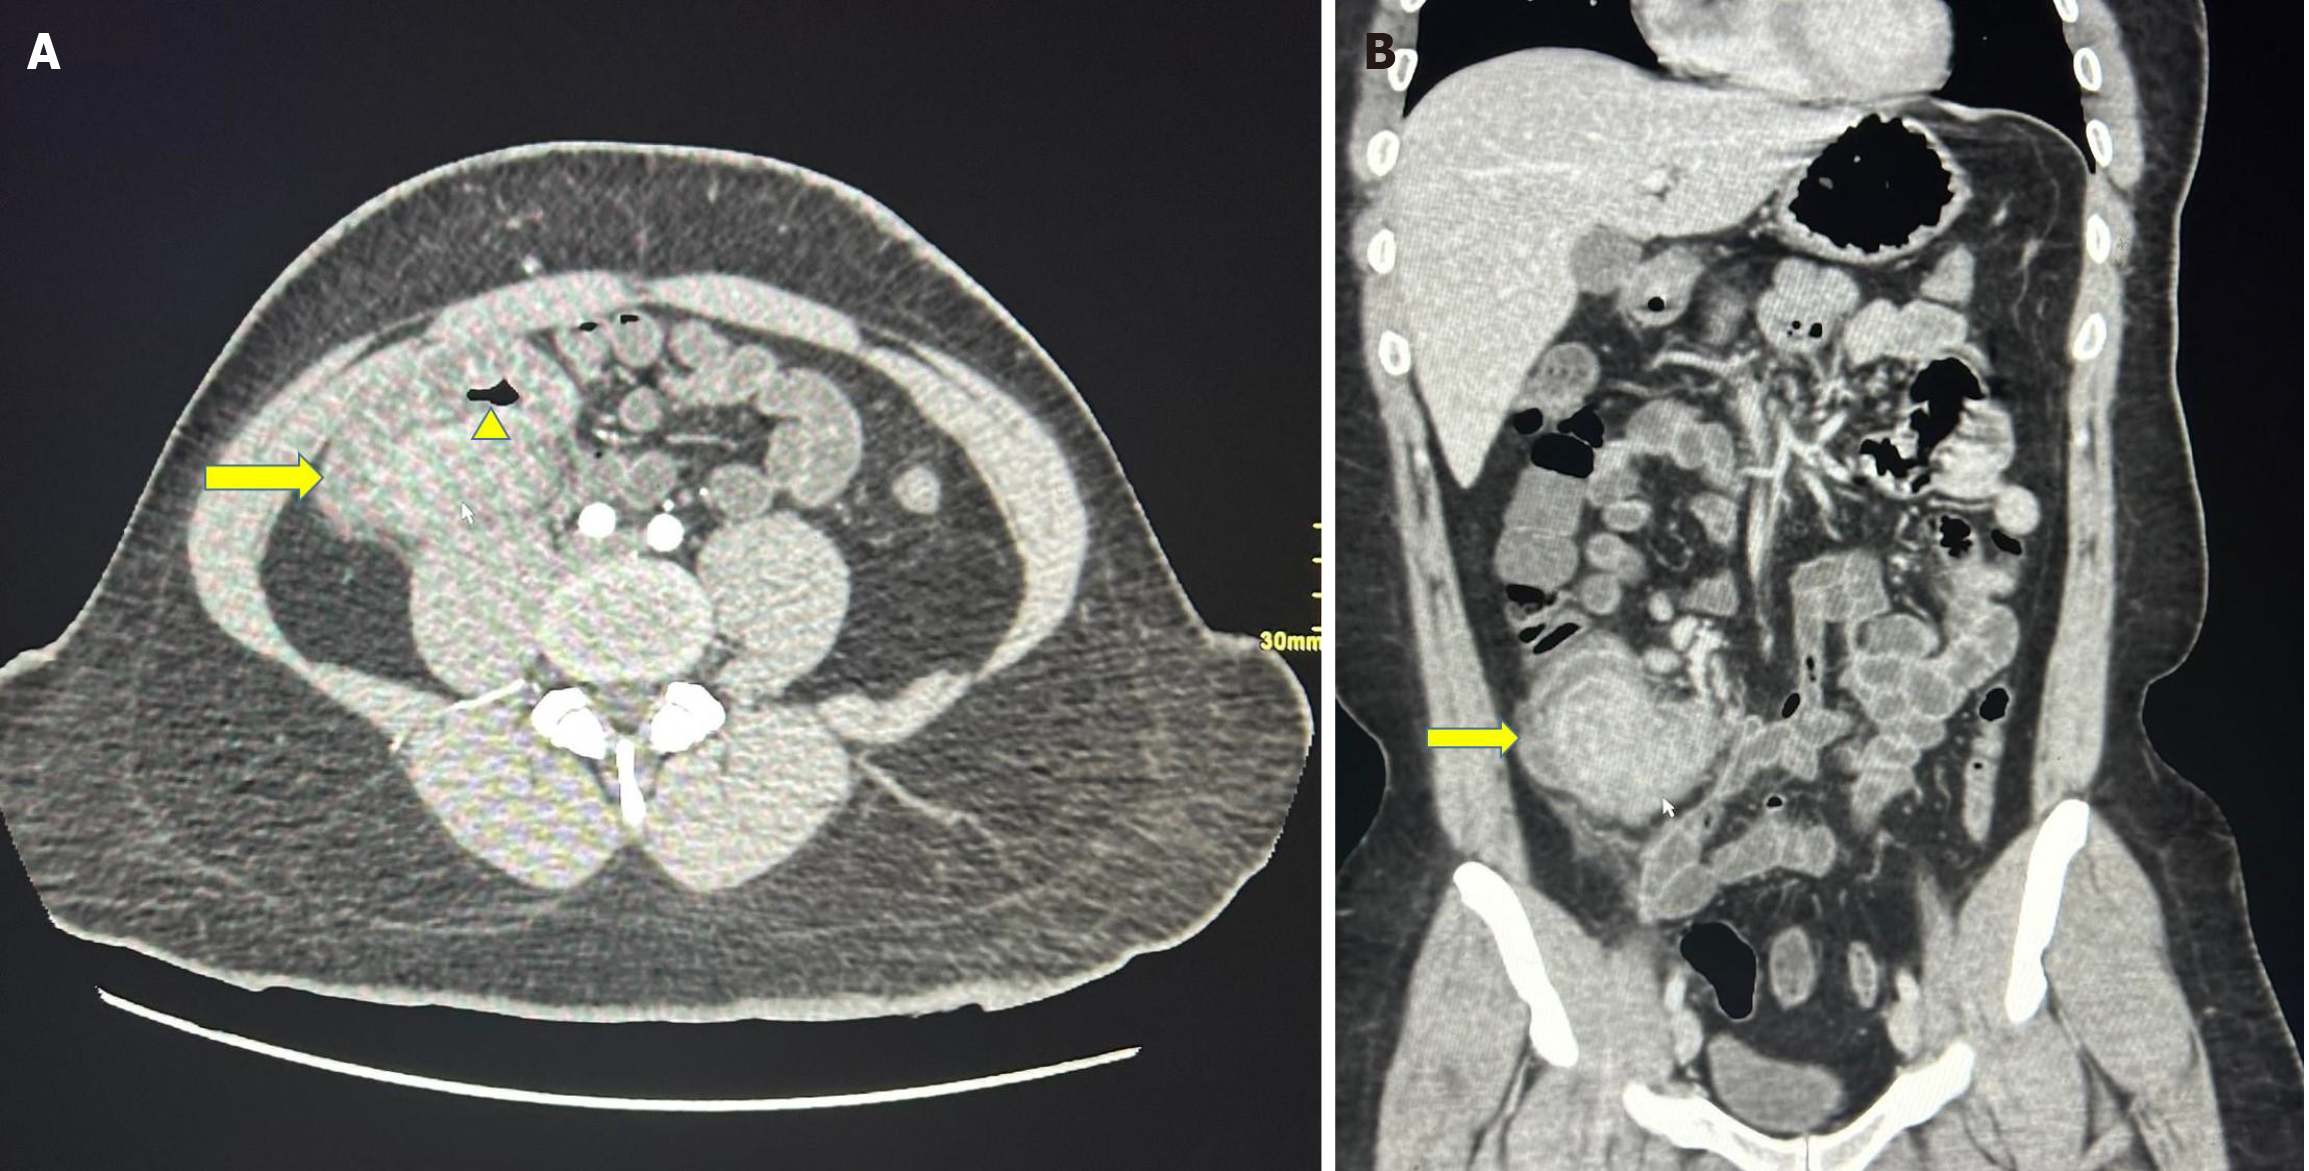

Figure 1 Computed tomography scan.

A: The axial section of the computed tomography (CT) scan shows a mass lesion involving the ileocecal region (yellow arrow) without complete obstruction of the intestinal lumen (yellow arrowhead); B: The coronal section of the CT scan shows a mass lesion involving the ileocecal region (yellow arrow).